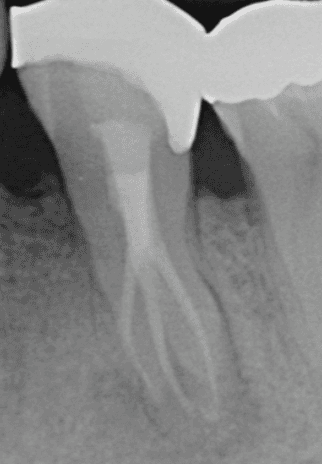

KREENA'S CASES